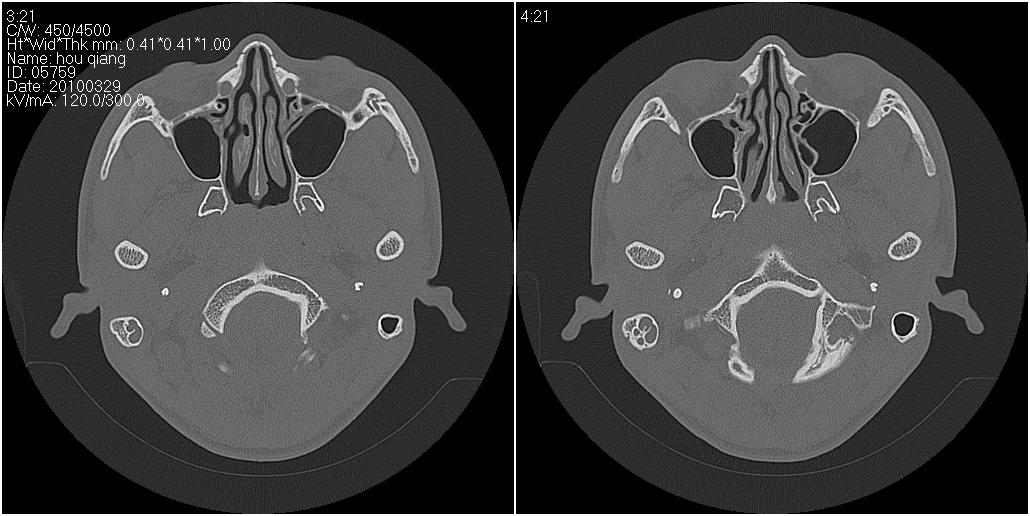

标题: CT25419:男性,18岁。右耳肿、痛5个多月。 [打印本页]

标题: CT25419:男性,18岁。右耳肿、痛5个多月。

右侧中耳乳突炎累及外耳道,鼻咽腺样体肥大。

1)右侧慢性中耳乳突炎并右侧中耳腔及外耳道肉芽肿或胆脂瘤形成。2)鼻咽腺样体肥大。